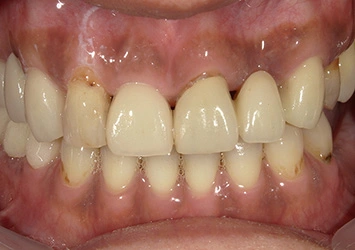

治療前

治療前写真 恵比寿南DENTAL

治療後

治療後写真 恵比寿南DENTAL

施術内容

【40代女性】

右上の前歯が歯根破折となっしまった為抜歯を行い、抜歯と同時にインプラント埋入を行った

治療期間

3ヶ月

リスク

術中の不可抗力によるトラブル(出血など)、術後注意事項を守らないことによる疼痛、感染、上部構造装着後口腔内清掃を怠ったことによるインプラント周囲組織の炎症

副作用

治療後の口腔内清掃、及びメインテナンスを怠ったことによるインプラント周囲粘膜炎またはインプラント周囲炎

費用

インプラント埋入:30万円

ジルコニアオールセラミッククラウン:15万円